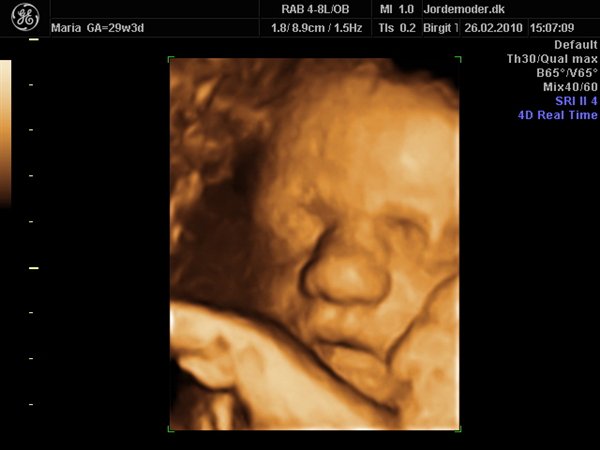

Idag har vi jo set lille pigen i 3d/4d, og hvor var det bare den mest fantastiske oplevelse..

Hun er bare så smuk og dejlig, med de fineste ballon kinder..

Her kommer lige lidt billeder af vores smukke datter..